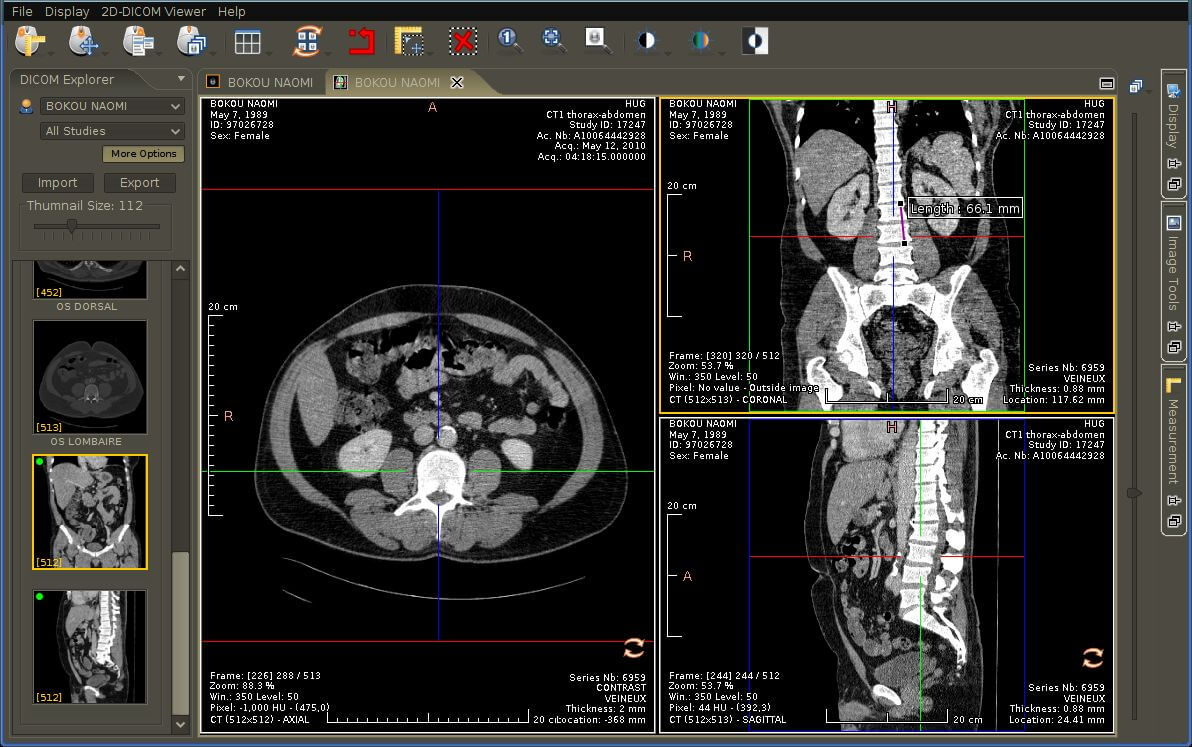

The RadiAnt DICOM image viewer is a simple, fast platform that is compatible with Windows. It offers multiple features, including MPR, MIP, and image fusion. Images can be exported to JPEG, PNG, and other image formats. They can also be copy-pasted directly to presentations and word documents.

The application is just a viewer and does not offer storage space. Their website has a disclaimer explicitly stating that they do not have any certifications, and as such, the product is not intended for diagnostic use. However, it is handy for students and residents for studying medical images and research purposes.